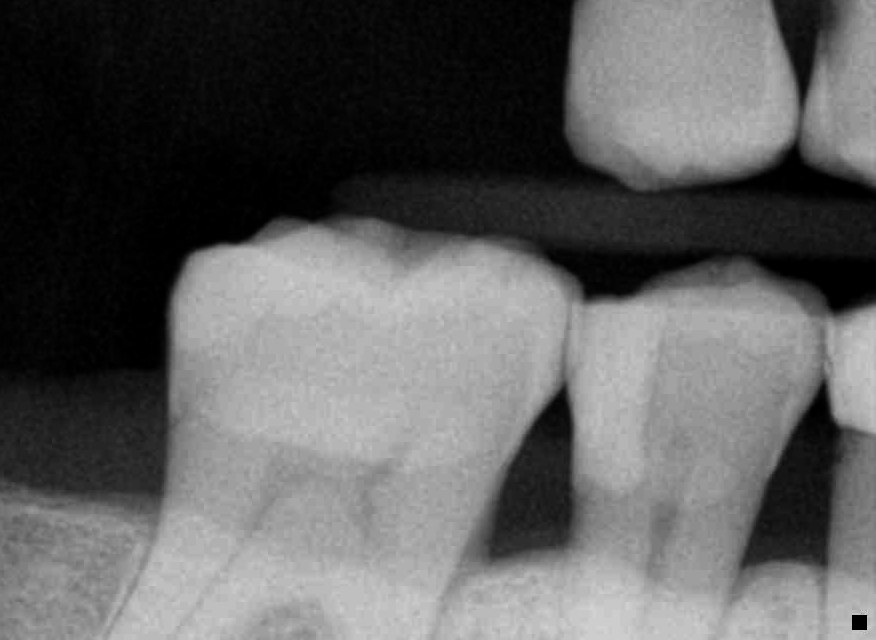

Bicon implant placement and restorations

#30 Bicon implant placement and restoration.

#12 extraction and placement of Bicon implant

#13 had old PFM crown which had amalgam overhang under the mesial margin that was causing food trap and periodontal issues. I opened up the crown, removed the overhang and lowered the margin and replaced with full zirconia crown on #13 for better longevity.